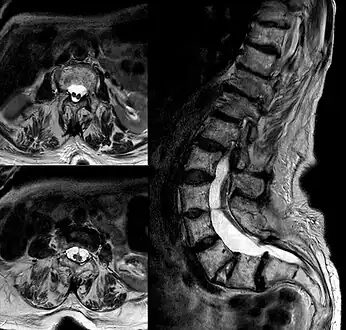

Adult presentation in diastematomyelia is unusual. With modern imaging techniques, various types of spinal dysraphism are being diagnosed in adults with increasing frequency. The commonest location of the lesion is at first to third lumbar vertebrae. Lumbosacral adult diastematomyelia is even rarer. Bony malformations and dysplasias are generally recognized on plain x-rays. MRI scanning is often the first choice of screening and diagnosis. MRI generally give adequate analysis of the spinal cord deformities although it has some limitations in giving detailed bone anatomy. Combined myelographic and post-myelographic CT scan is the most effective diagnostic tool in demonstrating the detailed bone, intradural and extradural pathological anatomy of the affected and adjacent spinal canal levels and of the bony spur.

Diastematomyelia usually occurs between 9th thoracic and 1st sacral levels of the spinal column with most being at the level of the upper lumbar vertebra. Cervical diastematomyelia is a very rare entity. The extent (or length of spinal cord involved) varies from one affected individual to another. In approximately 60% of patients with diastematomyelia, the two hemicords, each covered by an intact layer of pia arachnoid, travel through a single subarachnoid space surrounded by a single dural sac. Each hemicord has its own anterior spinal artery. This form of diastematomyelia is not accompanied by any bony spur or fibrous band and is rarely symptomatic unless hydromyelia or tethering is present. The other 40% of patients have a bony spur or a fibrous band that passes through the two hemicords. In these cases, the dura and arachnoid are split into two separate dural and arachnoidal sacs, each surrounding the corresponding hemicord which are not necessarily symmetric. Each hemicord contains a central canal, one dorsal horn (giving rise to a dorsal nerve root), and one ventral horn (giving rise to a ventral nerve root.) One study showed the bony spur typically situated at the most inferior aspect of the dural cleft. They advised that if the imaging appears to show otherwise, a second spur (present in about 5% of patients with diastematomyelia) is likely to be present.

The conus medullaris is situated below the L2 level in more than 75% of these diastematomyelia patients. Thickening of the filum terminale is seen in over half of the cases. While the level of the cleft is variable, it is most commonly found in the lumbar region. The two hemicords usually reunite caudally to the cleft. Occasionally, however, the cleft will extend unusually low and the cord will end with two separate coni medullarae and two fila terminale ("Diplomyelia").